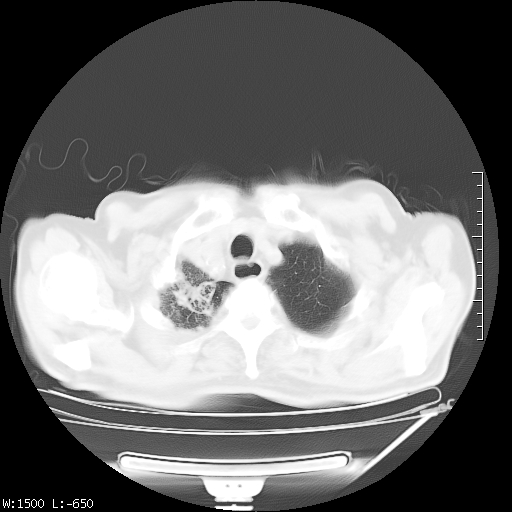

标题: CT23994:男、72、咳嗽、气短两月余,近来消瘦。 [打印本页]

标题: CT23994:男、72、咳嗽、气短两月余,近来消瘦。

tb可能性大(双肺均可见片状密度增高灶,其内可见低密度空洞)。

右上肺大片状密度增高影,与胸膜关系密切,内见低密度透亮影,胸膜下可见三角形不张影,左下肺沿支气管走形结节影,纵膈内淋巴结显示。考虑结核并疤痕性不张可能性大,建议穿刺活检,排除肺泡癌。